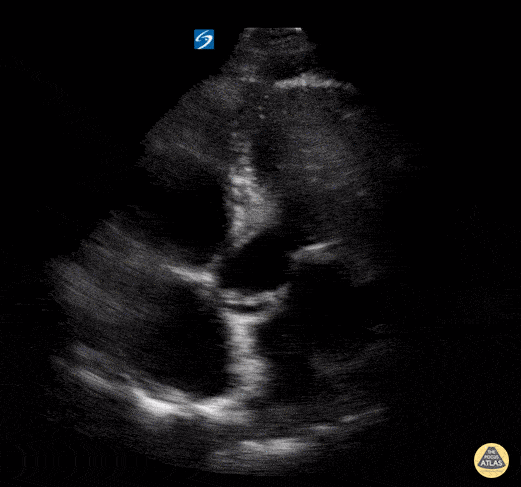

Normal Cardiac Anatomy - Apical 5 Chamber - Normal

In this view we are able to visualize all four chambers of the heart. Clockwise from the top left of the screen we see the right ventricle, left ventricle, left atrium, and right atrium. We can also see the tricuspid valve between the RA and RV and the mitral valve between the LA and LV. The “fifth chamber” is the aortic valve/root which can be appreciated in the center of the image. Hannah Kopinski - MS4, Dr. Lindsay Davis - NYU/Bellevue Department of Emergency Ultrasound, Dr. Matthew Riscinti - Kings County Emergency Medicine